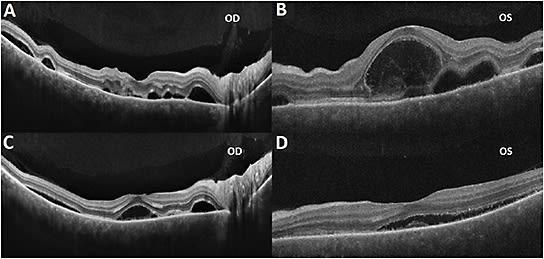

A 50-year-old healthy Asian female presented to clinic with blurry vision, floaters, and photopsia in both eyes (OU) that started 3 days previous. Her only ocular history was having LASIK surgery OU, and she denied any history of being diagnosed with uveitis or having uveitis symptoms. On day 1 of presentation, her best-corrected visual acuity (BCVA) was 20/25 in the right eye (OD) and 20/30 in the left eye (OS). Anterior chamber examination was notable for 1+ cell and flare in each eye (OU), and both eyes had 1+ vitreous cell with trace haze. Fundus exam revealed bilateral multifocal serous detachments and pigment epithelial detachments (PEDs) with creamy, deep lesions in the posterior pole of the macula. Macular ocular coherence tomography (OCT) demonstrated multifocal lobular serous detachments, PEDs, and thickened choroid OU (Figure 1).

On day 8 the patient reported improvement, with BCVA now 20/30 OD and 20/40 OS. Exam findings improved, as did OCT scans, which showed regressing subretinal fluid, PEDs, and bacillary layer detachments (Figure 3). The uveitis workup was complete and unremarkable.

On day 14, the patient’s exam and BCVA continued to improve to 20/25 OD and 20/30 OS. Both eyes had complete resolution of anterior chamber and vitreous inflammation. Oral and topical steroid tapering was initiated. Three months after presentation, the patient was successfully weaned off all medications with BCVA restored to her baseline of 20/20 OU. Both eyes were quiet and appeared normal on exam, and OCT showed a profound normalization without any fluid, PEDs, or choroidal thickening (Figure 4). The patient has not had any recurrences since the initial presentation and has now been stable for over 1 year.